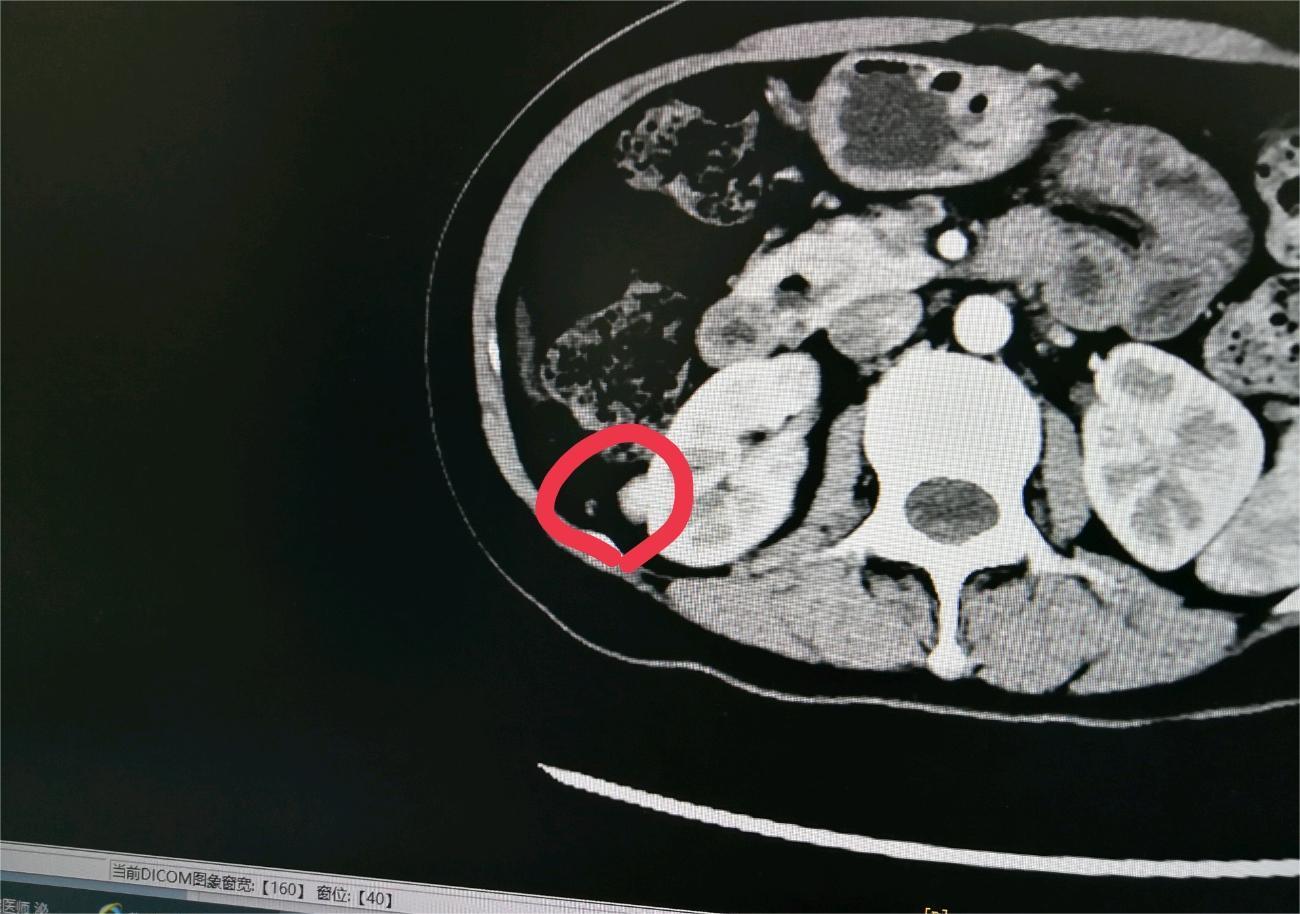

爱你的形状 02024-02-07 患者家属我2岁的女儿通过超声检查发现右肾有个肿瘤,在北京儿童医院做手术,肿瘤术中检测是小圆细胞恶性肿瘤,右肾已摘除,现在术后2天...

花谢花开花满楼 02024-01-30 患者家属 -